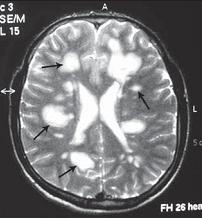

МРТ № 30

На МРТ № 29 наблюдаются протрузии и грыжи межпозвонковых дисков в шейном отделе позвоночника На МРТ № 30 головного мозга этого же пациента наблюдаются очаги демиелинизации вследствие развития нейроинфекции